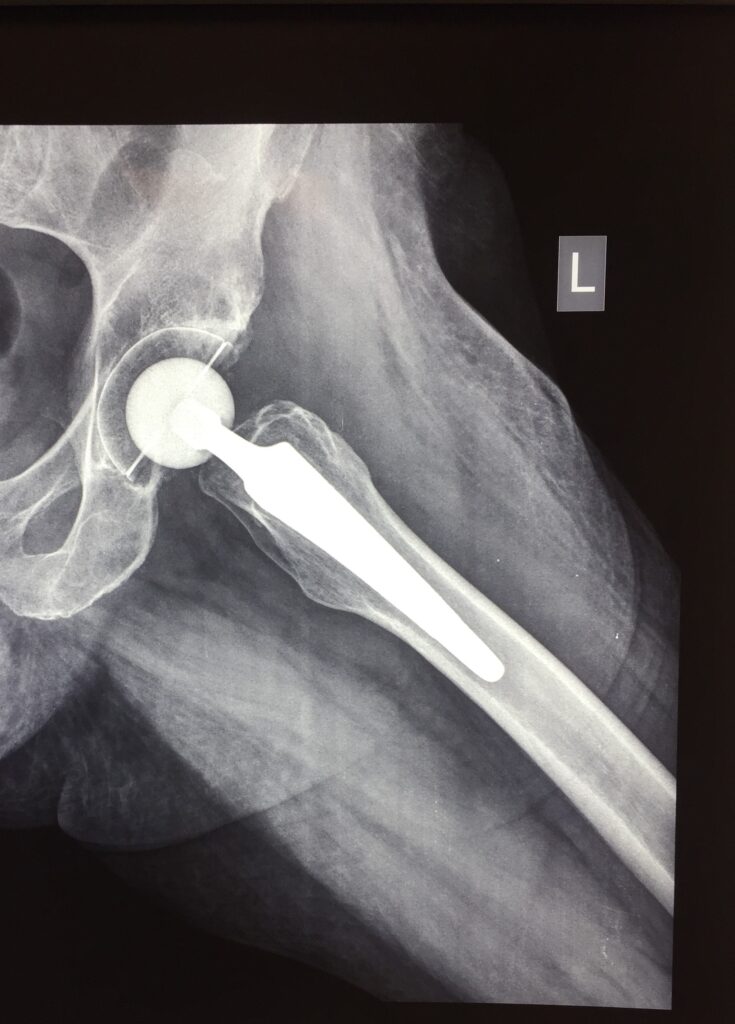

Η αρθροπλαστική Ισχίου είναι η επέμβαση αντικατάστασης των φθαρμένων τμημάτων της άρθρωσης του ισχίου με μια τεχνητή άρθρωση. O σωστός προσανατολισμός στην τοποθέτηση των προθέσεων, η ακριβής αποκατάσταση του μήκους και η απαιτούμενη τάση των μαλακών μορίων αποτελούν προϋπόθεση για την επιτυχία της ολικής αρθροπλαστικής του Ισχίου.

- Επανεξέταση με ακτινογραφία σε 6 εβδομάδες